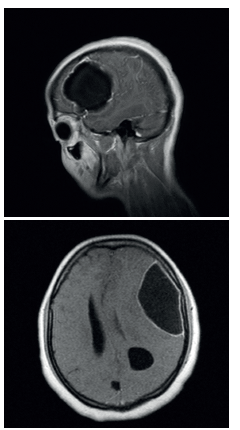

En la Imagen de RMN simple y contrastada (Figura 1) en secuencias de T1, se aprecian lesiones expansivas quísticas intraparenquimatosas cortico-subcorticales y periventriculares a nivel supratentorial; algunas de ellas con tejido interno compatible con neurocisticercosis. La lesión más prominente de tipo corticosubcortical frontotemporal izquierda, con contenido líquido no homogéneo y septaciones en su interior, con captación gruesa, intensa e irregular de su cápsula con discreto edema perilesional que desvía la línea media, colapsaba parcialmente el ventrículo lateral izquierdo y comprimía el tercer ventrículo. Razones por las cuales se decidió iniciar manejo con albendazol genérico, a dosis de 15 mg/ kg/día según lo establecido por el Centers for Disease Control and Prevention (CDC), asociado a medidas antiedema. Teniendo en cuenta el tamaño de la lesión, el compromiso motor y la desviación de la línea media, se decidió llevar a la paciente a drenaje quirúrgico de la lesión intraparenquimatosa fronto-parietal izquierda.